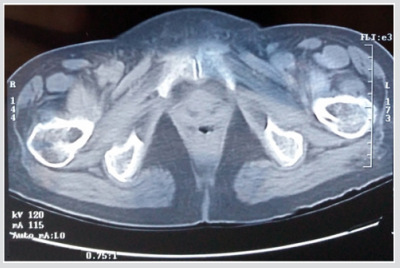

For the current study, one human cadaver was selected from a 65-year-old male with the stature and weight of 180 cm and 84.5 kg respectively. This subject has the characteristic mass and stature close to the average adult male and cause of dearth was carcinoma of the heart. In the current study geometry of the left proximal femur complex has been scanned by CT scanner, with examination showing no signs of metastases or other abnormalities such as previous fractures present in the femur. Following initial examination, the left proximal femoral specimen was removed from the cadaver for in vitro CT scan. The in vivo and in vitro data was collected by the department of Radiology, Milad hospital, Tehran, Iran. From the CT scan, shown in Figure 1, cortical and cancellous bone can be distinguished, alongside soft tissue such as muscle. The CT scan also provided data in terms of bone density shown in Figure 2. The initial data was collected using the following parameters: Siemens, 110 kVp, 105 mAs, 5 mm thick slices at 2.5 mm interval, total of 255 slices, with an in-plane resolution of 0.7mmx0.7mm (pixel size). For in vitro CT scan of the of femur specimen the soft tissue was removed and immersed in water to maintain the properties of the femur as close to that of the femur in vivo, this will also reduce and cut down artefacts', see Figure 2. The in vitro CT scan in vitro used the same parameters as the in-situ scan, except that a pixel size of 0.75mm×0.75mm was used. This method has been used in previous studies, Keyak [10]. The different pixel sizes will not have influenced the study results because the image quality varies depending on the pixel spacing. The resolution is determined by the slice thickness and the finite elements, which are larger than the pixel size and therefore determined the overall model resolution. The 235 slices of the CT scan data of each femur is collected in the DICOM format (Digital Imaging and Communications in Medicine), which is then uploaded to, SIMPLEWARE (version 3.1Simpleware, UK), to produce the solid model, see (Figures 3 & 4). The output of the Simple ware software was converted into the DXF format and transferred to the IGS format by using FEA software, in this case ANSYS. Then, the IGS data of each solid model, both in situ and in vitro, was translated to generate a 3D- FE model of the human pelvis-femur complex. The FE modelling was conducted using finite element software LS-DYNA. LS PREPOST 3.1 was used to analyze the results and also to create the models in the pre/post-processor. The method of producing each of the FE models from CT scans, and mechanical testing procedures used in this study have been described in detail in a previous study, Razmkhah[11].